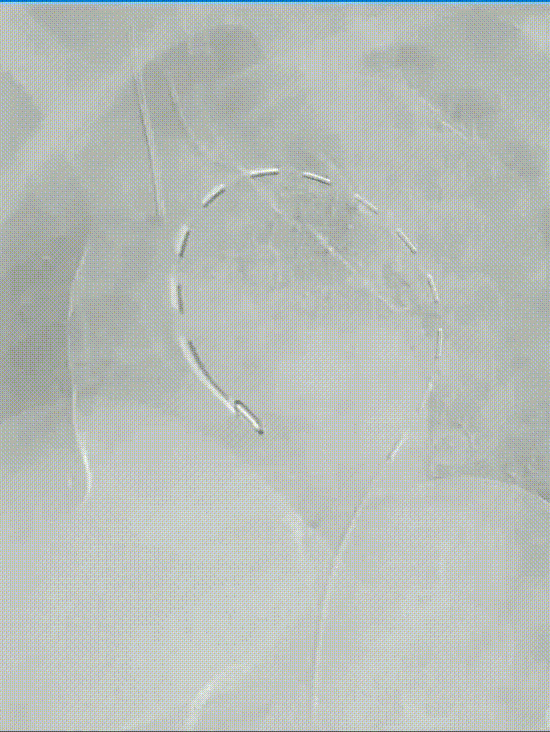

新型三分支胸主动脉覆膜支架示意图

★ 主体支架(Mainbody)

无名动脉外分支与双内嵌分支:主体支架由1个一体式无名动脉外分支与2个内嵌分支组成(分别对应左颈总动脉LCCA和左锁骨下动脉LSA),内嵌分支结合顺行与逆行技术,减少内漏风险(尤其是III型)。

下沉区(Sinking Zone):预留空间便于LCCA和LSA分支支架导入和展开,并适应不同LCCA与LSA间距的解剖变异。

血流动力学优化:通过内嵌分支通道维持头臂干(IA)顺行血流,降低剪切应力,减少术后并发症。